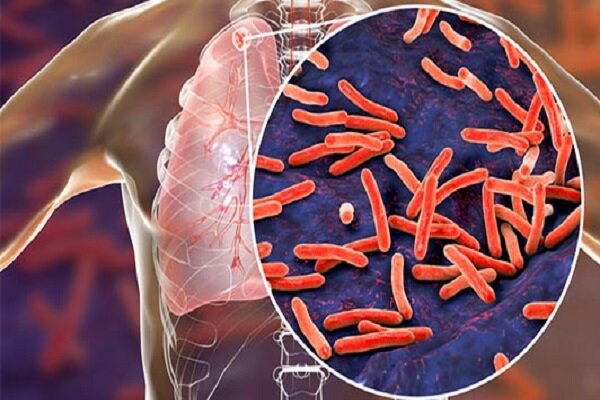

سل یک بیماری عفونی مسری است که توسط باکتری ها ایجاد می شود باکتری سلولی این بیماری بروز می کند ، این بیماری بیشتر ریه ها را تحت تأثیر قرار می دهد و از طریق ذرات تعلیق هوا به ویژه در هنگام سرفه یا عطسه فرد مبتلا منتقل می شود ، و اگرچه سل در بسیاری از کشورها کنترل می شود ، اما هنوز هم یکی از اصلی ترین دلایل مرگ در جهان است ، به خصوص در جوامع با شدت بالا ، مهاجرت یا ضعف گسترده ای از وقایع بهداشتی.

موقعیت کشور در کنترل سل ؛ به آمار جهانی نگاه کنید

به گفته سازمان بهداشت جهانی ، شیوع سل در ایران حدود 5000 نفر در هر جمعیت است و به گفته قباد مرادی ، رئیس مرکز بهداشت و درمان مدیریت بیماری های عفونی ، این تعداد نشان می دهد که عملکرد موفق کشور در کنترل این بیماری ، به ویژه در مقایسه با کشورهای همسایه ، برخی از آنها در میزان بالایی هستند و این نتیجه آموزش عمومی آزاد و آموزش آزاد بوده است.